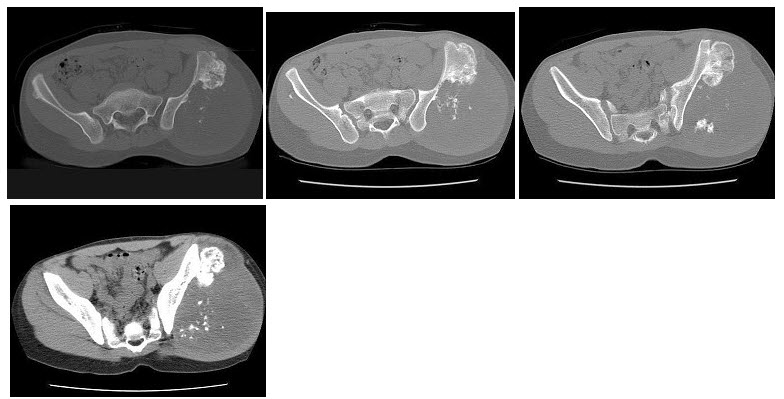

8、单项选择题

男,13岁,右髋部疼痛不适,无红肿,结合所提供的图像,最可能的诊断是()

A.非骨化性纤维瘤

B.骨巨细胞瘤

C.畸形性骨炎

D.内生软骨瘤

E.骨纤维结构不良